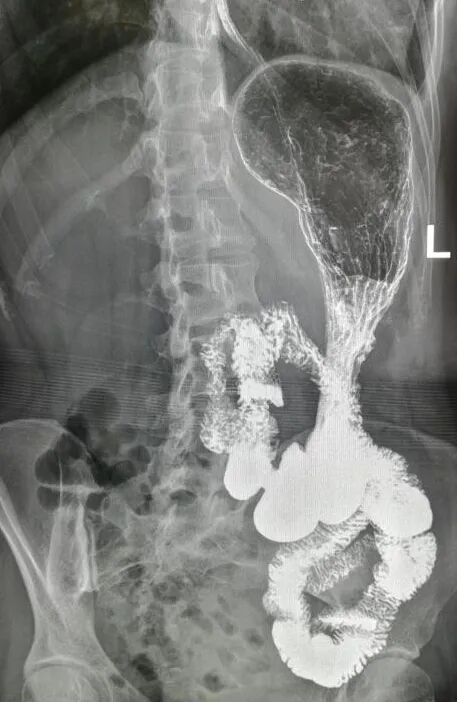

上腹部疼痛1年 ,胃镜检查见两个十二指肠开口,无手术史,建议钡餐检查